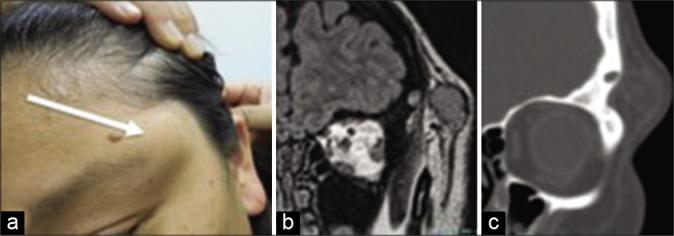

CASE DESCRIPTION

A 43-year-old female presented with recurrent subcutaneous mass in the left superolateral orbital region. She had a history of active bronchial asthma, which precluded her from contrast-enhanced imaging studies. Plain imaging studies showed a subcutaneous mass which was continuous with an intrasylvian fissure mass by a tract in the sphenoid ridge and the lesser wing of the sphenoid bone. Frontotemporal craniotomy was performed to reset the mass and the tract. Intraoperative finding showed no intradural tumor components. Extradural component was carefully removed focusing attention on the frontal branch of the facial nerve. The pathology was consistent with dermoid cyst and dermal sinus tract. Postoperatively, she had mild facial palsy of the corrugator supercilii (House and Brackmann Grade II). She was discharged home with modified Rankin scale 1.

病例描述

一名43岁女性,左眶外上区域反复出现皮下肿块。她有活动性支气管哮喘病史,这使得她无法进行增强成像检查。平扫影像学检查显示一个皮下肿块,通过蝶骨嵴和蝶骨小翼的一个管道与大脑外侧裂内的肿块相连。行额颞部开颅手术以复位肿块和管道。术中发现无硬脑膜内肿瘤成分。硬膜外成分被小心切除,重点关注面神经额支。病理结果符合皮样囊肿和皮样窦道。术后,她出现了皱眉肌轻度面瘫(House和Brackmann分级II级)。她出院时改良Rankin量表评分为1分。